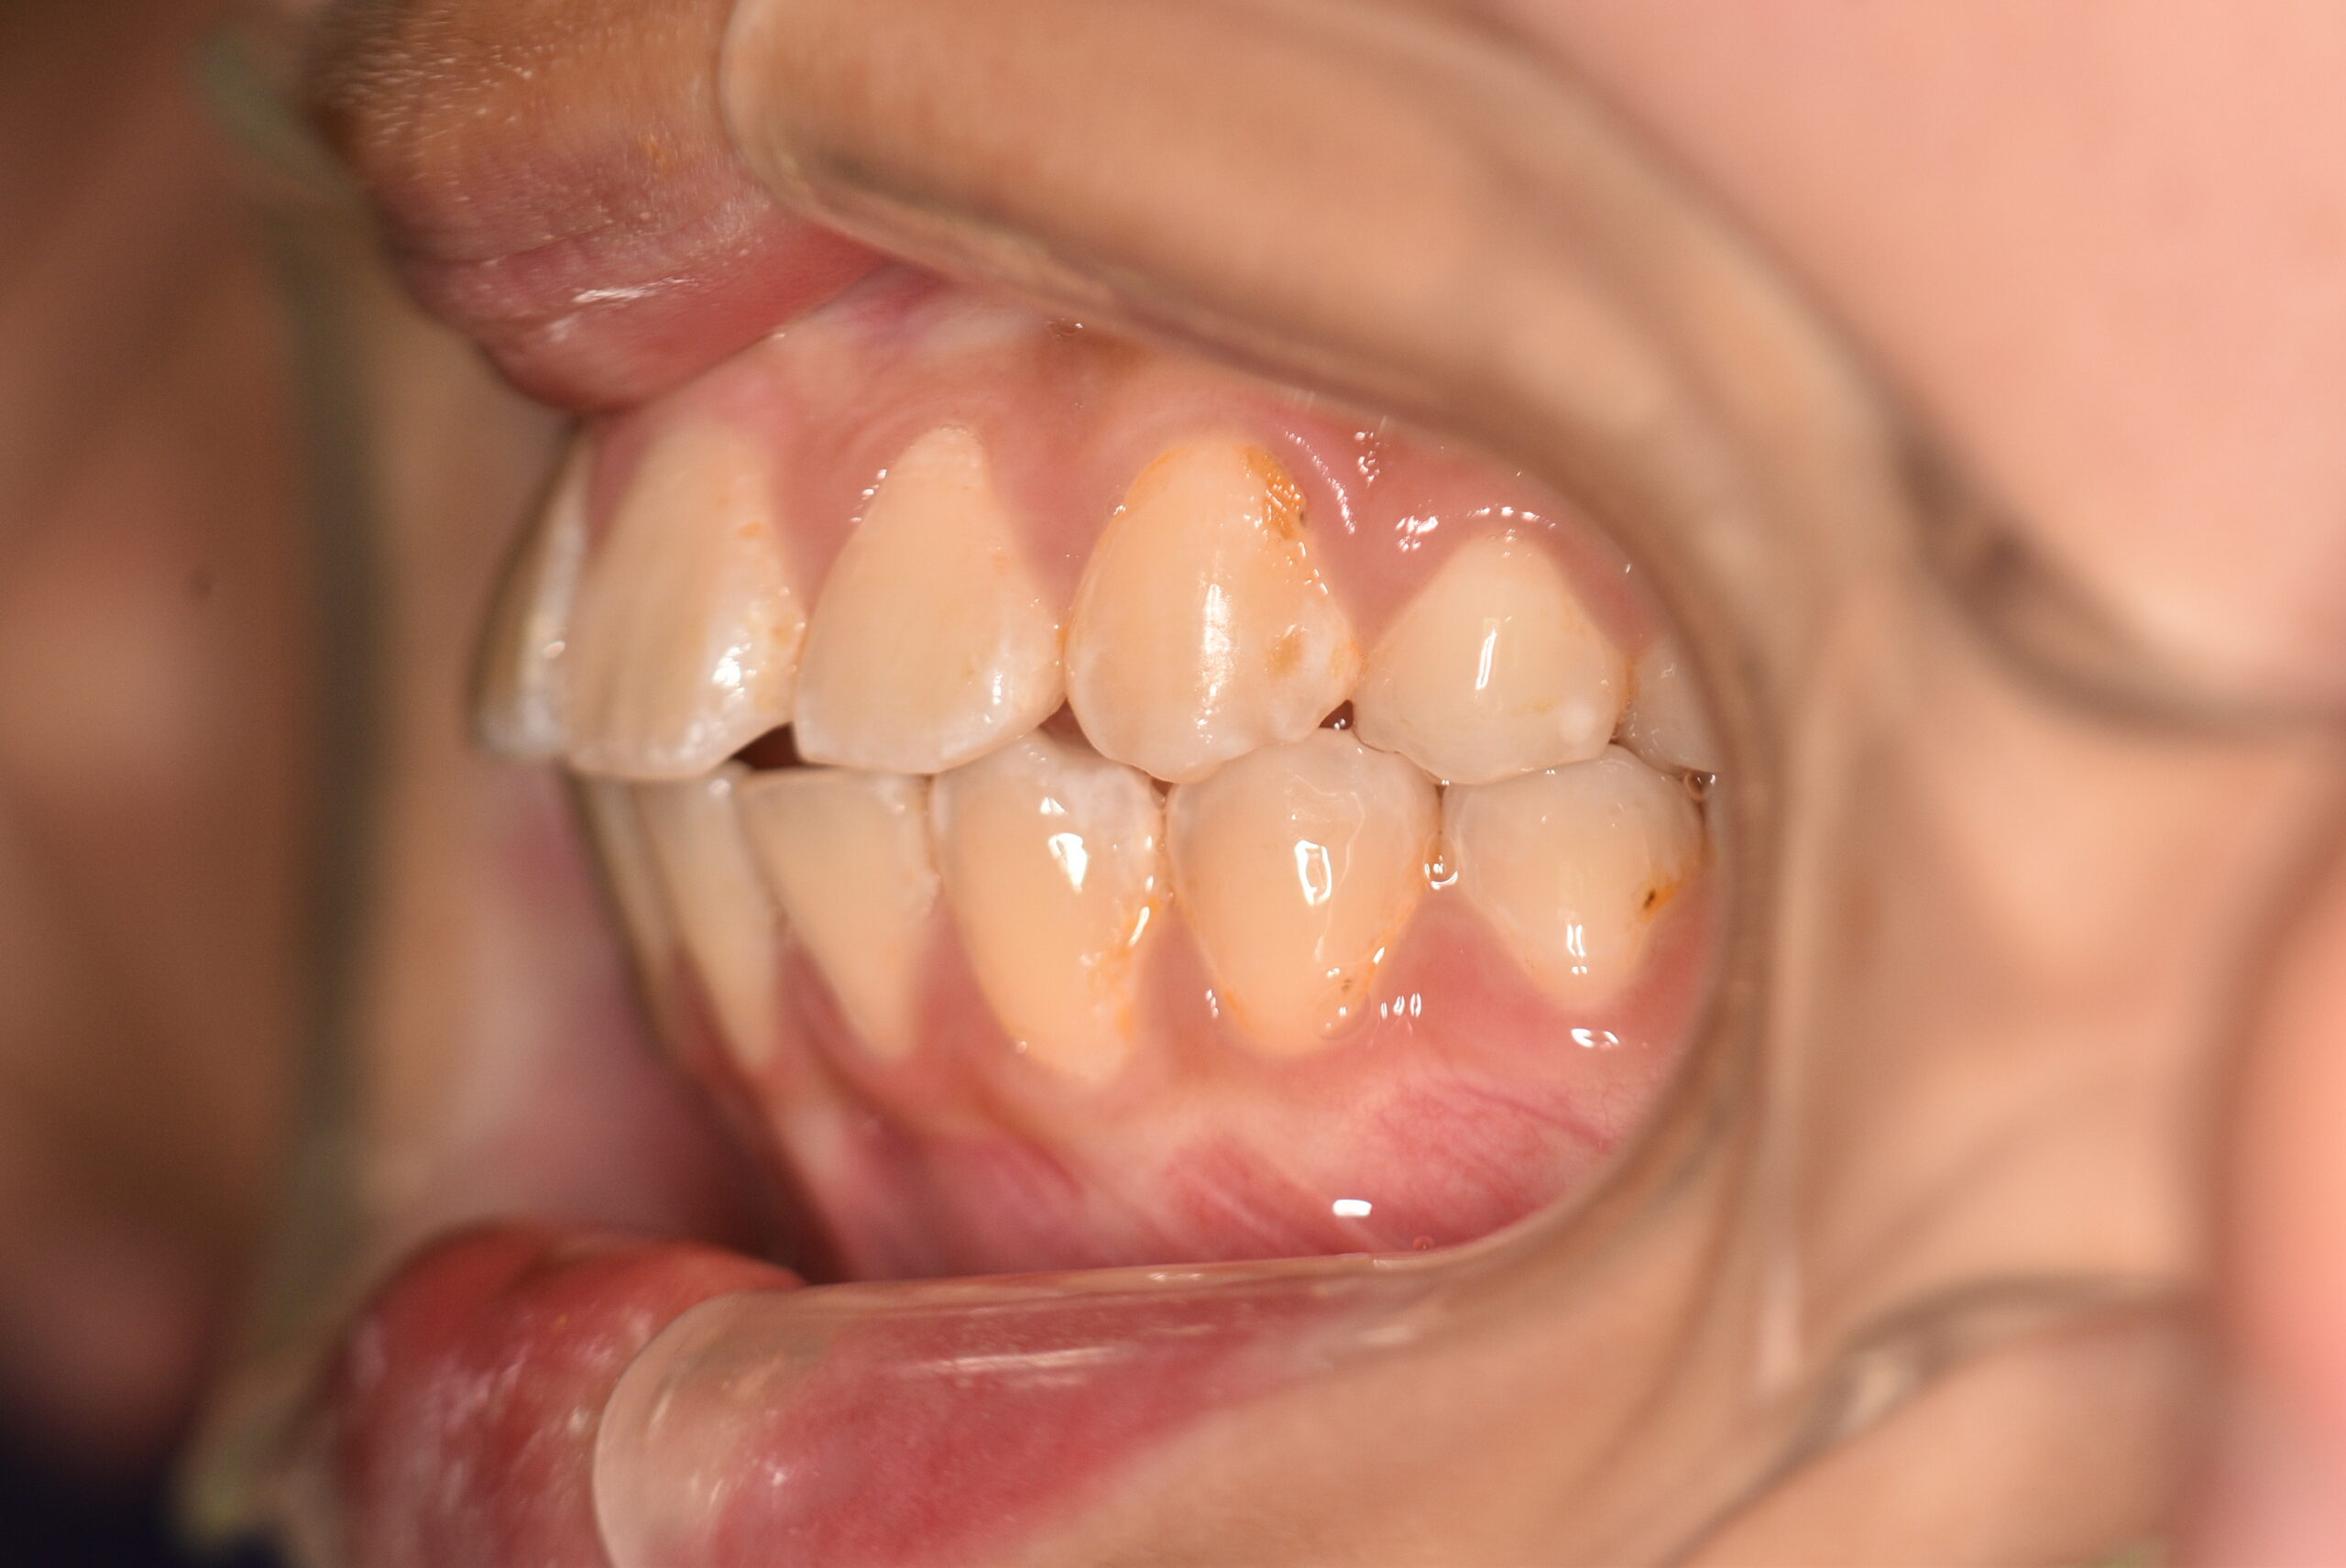

| 治療内容の詳細 | 初診時12歳の女性で、歯並びが悪く歯が磨きにくいことを気にされ来院されました。 検査の結果、上顎前突及び上下顎前歯部叢生を伴うアングルⅡ級1類不正咬合と診断しました。 治療としては、上顎左右第1小臼歯を抜歯し、セルフライゲーションブラケット装置(デーモンシステム)で歯の配列を行いました。 同時に顎間ゴムにて咬合関係の改善を行いました。 治療期間は、2年6ヶ月でした。 |